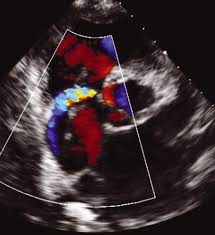

심장 초음파는 인체에 무해한 초음파를 이용해 실시간으로 이러한 심장의 움직이는 모습을 관찰할 수 있고 심장의 움직임과 구조, 혈류의 흐름, 판막의 이상 유무 등을 비침습적으로 관찰할 수 있는 검사법이라고 한다. 대부분의 심장 질환에 필수적인 검사며, 많은 심장질환에서 높은 정확도를 가진다고 한다.

심장 초음파로는 혈액의 역류를 막아주는 4개의 판막이 잘 열리고 잘 닫히는지, 구멍 등 이상 소견은 없는지, 혈액의 역류는 없는지 등을 확인할 수 있다고 한다.